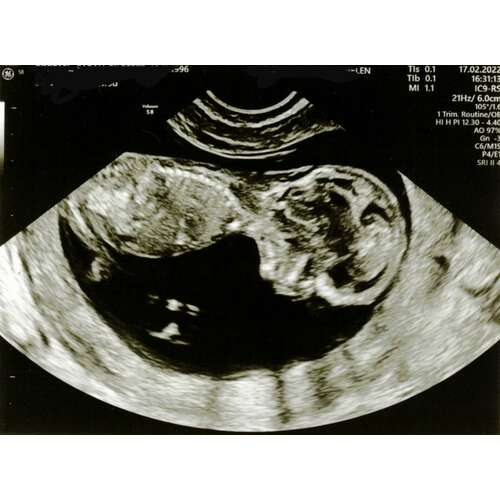

@nubster ik heb er nog 3 maar daarna is het ook echt gedaan dus dan moet ik maar wachten tot de nipt terug komt 🙈🙈

2

3

Hier nog wat foto’s🙂